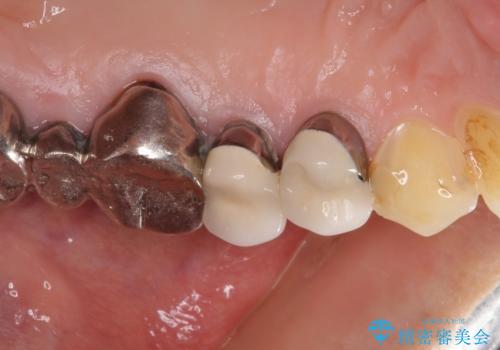

- 歯肉が退縮したためにクラウンの縁や歯根が見えてしまっていることを気にして来院された患者様です。

仮歯に変えた後にオールセラミッククラウンにて補綴することとしました。

強い咬合力や磨きすぎなどにより、歯根が見えてしまったり、金属の縁が見えてしまったりし、審美障害を引き起こすことがあります。

歯根が変色してしまうと、歯肉越しに歯根の黒い色が透けてしまうことがあり、この点についてはどうにも施しようがないため、患者様には事前のご理解いただきました。

治療前と比べてとても自然な前歯となり、患者様には大変満足していただきました。